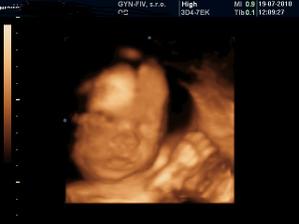

@grenka ale pekne bruchane...pri chalanovi zvykne byt zena pekna a priberie viacmenej len do bruska...ze nie je to rozliate vsade..tak aspon nejake pozitivum...tie uzv na stanovenie hmotnosti su len orientacne...v 31tyzdni mi povedali ze 2080 a v 32tyzdni ze 1800...chapes...?akoze to za tyzden...co mal este pribrat tak schudol...xixi...a odvtedy mi nikto nerobil uzv...ale objednala som sa sukromne bud tyzden...tak uvidime kolko bude mat